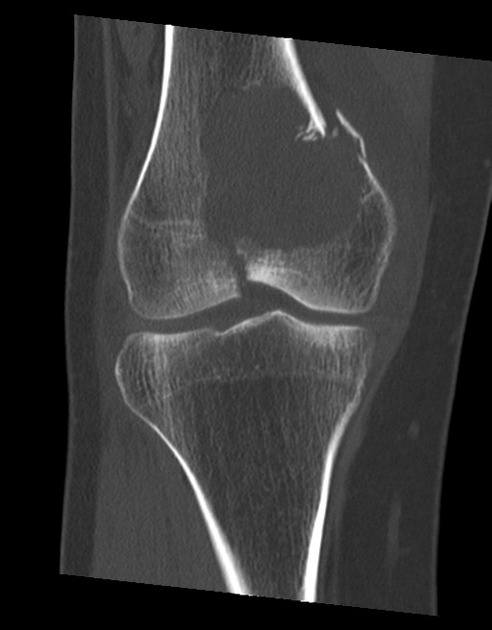

U tế bào khổng lồ

» Thông tin: Nữ giới – 31 tuổi.

» Lâm sàng: Đau khớp gối.